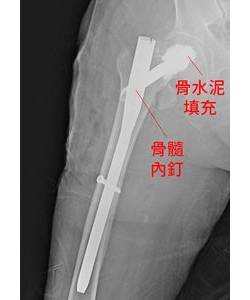

九旬翁髖部骨折 髓內釘搭配骨水泥治療6天出院可行走

許皓為醫師指出,骨髓內釘搭配骨水泥治療,可加強骨髓內釘穩定度,能彌補髖部骨摺合併骨鬆的患者骨折不癒合的問題,帶來更高的負重承載力、抗拔除力,也大大提升治療成功率。 91歲的孫伯伯,獨自在家上廁所時不小心被門檻絆倒,由於年事已高、骨質脆弱,一跌就產生了髖部轉子間骨折。後來醫師判定他骨質密度不足,因此以骨髓內釘搭配骨水泥治療,術後兩天就能站立,第6天就出院...... [閱讀更多]